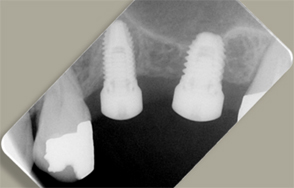

- インプラント埋入後のレントゲン写真